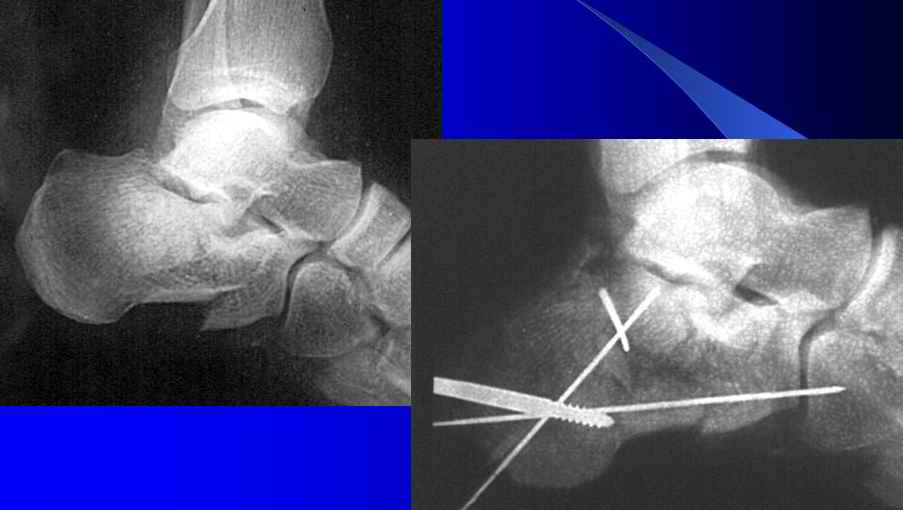

В Вашей ситуации мы бы выполняли чрескостный остеосинтез обеих пяточных костей.

Первый этап - это репозиция на операционном столе, причем для удобства репозиции со стороны пяточного бугра в косо-сагиттальных плоскости ввели бы 2 консольные короткие спицы. Они были бы и рычагом и органом управления отломками. После предварительной репозиции те же спицы могут быть проведены в таран или прочие кости для временной фиксации. Теперь R-графия и выбор компоновки.

На рисунке стандартная схема, но от ситуации могут быть варианты.

Второе - голеностопный сустав мы фиксируем. Это позволяет не <дырявить> таранную кость, а кольца на голени являются точкой опоры для дальнейших устранений угловых смещений.

Третье - передний отдел обычно тоже фиксируется, иначе восстановить свод стопы бывает проблематично.

В тело пятки спицы с упором на встречу друг другу, можно с перекрестом, а можно и параллелно, тогда будет большая управляемость

Еще мы иногда соединяем опоры переднего отдела и базу на пятке при помощи шарниров и резьбовых стержней. Это дает возможномть компенсации длины или переднезадней компрессии + устранения углов любой плоскости.